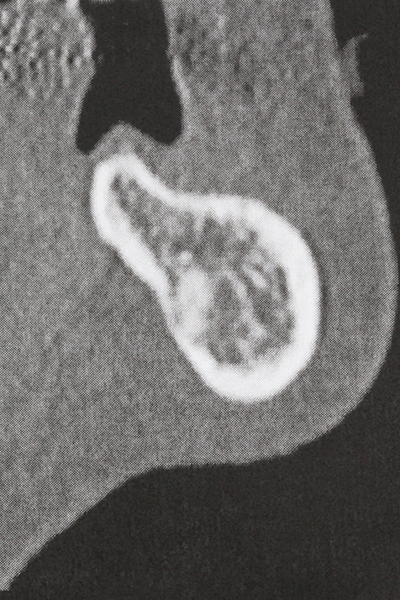

There are additional applications in sinus surgery. Pathologies and foreign bodies can be removed from the sinus after concentric preparation of a generally trapezoid bone cover in the facial sinus wall. The bone cover is repositioned on conclusion of the intra-antral operation component and secured by wedging or adaptive sutures to prevent dislocation.

Purely orthodontic indications include orthognathic surgery, genioplasty (Fig. 27-30) and orbital decompression in patients with advanced endocrine orbitopathy as a result of Basedow’s disease (Ponto, Zwiener et al. 2014). Piezo devices are also used in maxillofacial surgery and to remove tumours at the base of the skull in various hospitals.